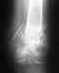

Здесь есть смысл сделать эндопротезирование. Не надо считать приговор окончательным, добивайтесь. Если пациентка до перелома самостоятельно ходила, она операбельна. Важно не дать развиться осложнениям от лежания. Так что лучше по мере уменьшения боли пациентку активизировать, ставить на костыли. Еще раз, положение отломков тут никакой роли не играет, не срастется в любом случае, так что не бойтесь смещения, главное - предотвратить пролежни, пневмонии и т.д.